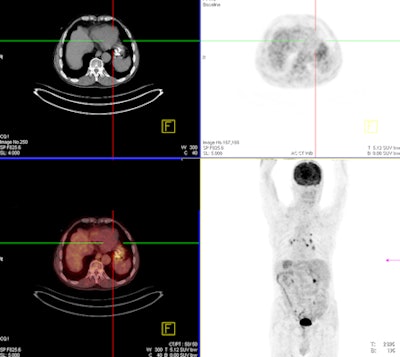

A 68-year-old man with an 8-mm distal esophageal mass with biopsy-proven squamous cell carcinoma. On coronal PET, axial PET, and axial fused PET/CT images (above), the primary tumor demonstrates no significant FDG uptake. Axial CT image shows esophageal mass at the same level. In the same patient, functional perfusion maps of blood volume, blood flow, and permeability surface (below) reveal the intratumoral perfusion distribution. CT perfusion values for blood volume (left), blood flow (right), and permeability surface (bottom) were 9.62 mL/100 mL, 86.67 mL/100 mL/min, and 12.65 mL/100 mL/min, respectively. All images courtesy of Dr. Mecit Kantarci.